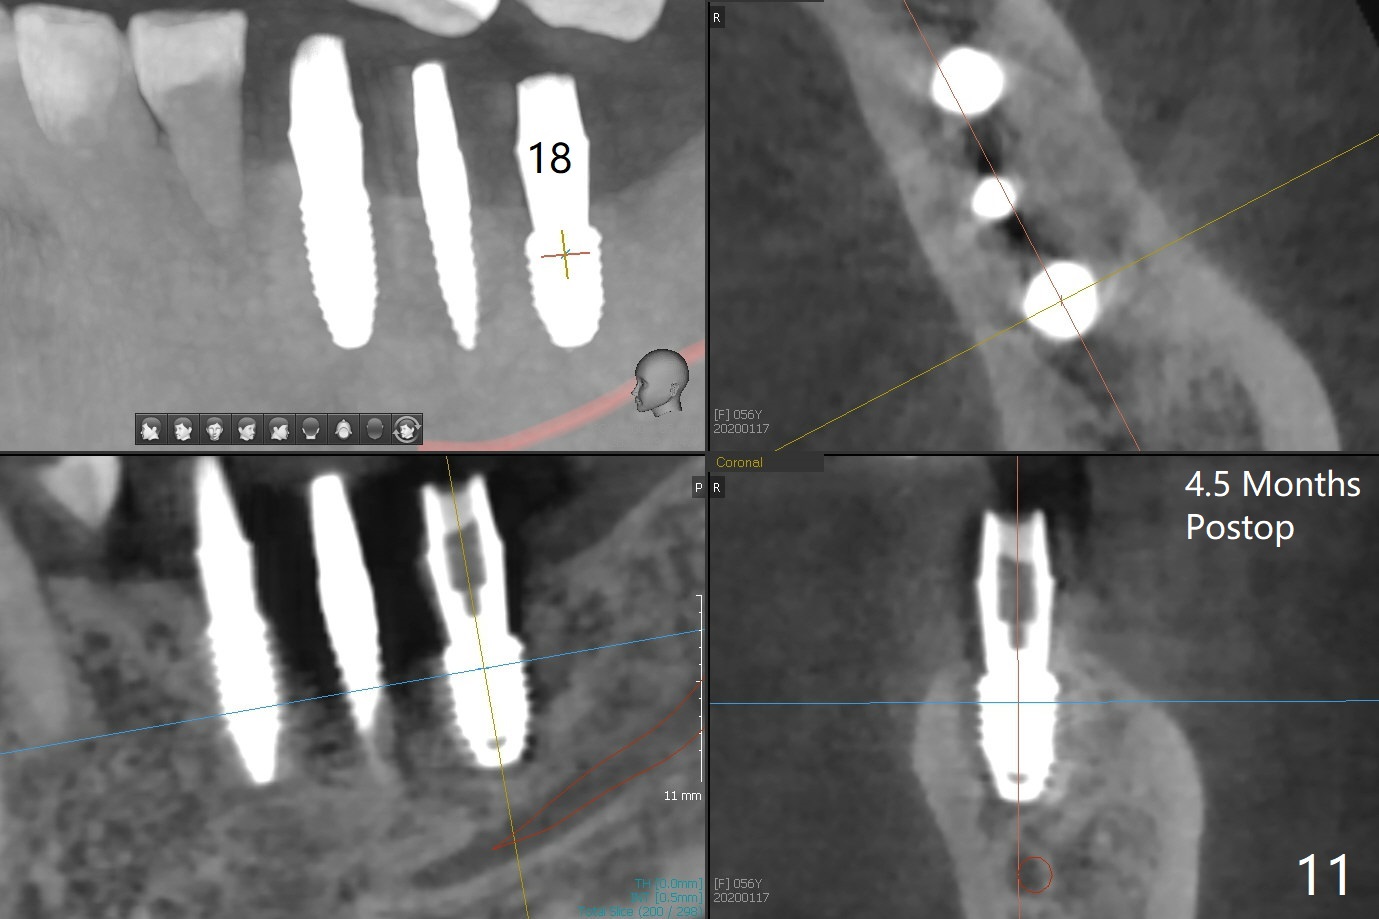

PA is taken after a 2.2 mm drill reaches the depth at #12, since osteotomy is initiated in the mesial slope of the socket (Fig.1 red dashed line) and the neighboring root (*) slightly curves distal. A 8.6x5 mm healing abutment is used to close the socket with the large mesiodistal space after bone graft (Fig.2 *). In contrast, the socket at #20 is large; a 4.5x4.5(3) mm cementation abutment is placed for an immediate provisional to keep autogenous bone (harvested from the site of #18) in place (Fig.3). Six months postop, the patient does not want implant FPD. She wants an additional implant at #19. Since the space between the implants #18 and 20 is 9.41 mm, a narrow implant is indicated (3 or 3.5 mm, Fig.4), in spite of the sufficient buccolingual width (Fig.5). The position and trajectory of the 1.2 mm initial drill and 3x10(2) mm 1-piece implant are acceptable with free hand (Fig.6,7). After 3-4 more turns, panoramic X-ray (Fig.8) and CT (Fig.9) are taken for 28-30 guide. It appears that the 1-piece implant is placed acceptable buccolingual (Fig.9 B). The implants at #12,18,20 (4.5 months postop with guide) are shown in Fig.10-12. It appears that guided surgery is superior in buccolingual position and trajectory to free hand. There is crestal remodeling without implant thread exposure 11 months postop (Fig.13).